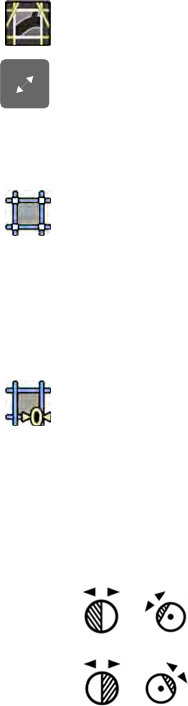

8.8.1 Zmiana maski subtrakcji.......................................................................................136

8.8.2 Dostosowywanie położenia maski....................................................................... 137

8.9 Korzystanie z funkcji wskazywania punktów orientacyjnych................................................137